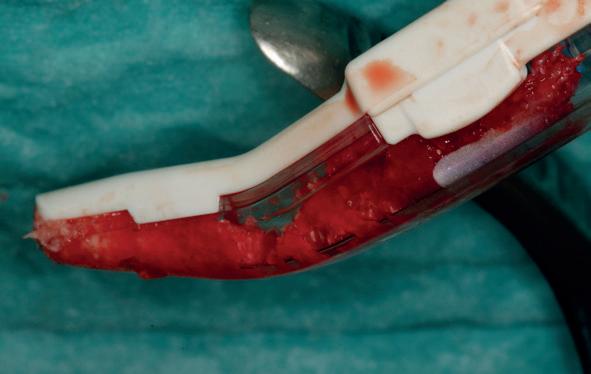

Voor de aanvulling zachte weefsels chirurgie werd gekozen voor de VISTA techniek, hierbij worden er twee incisies partial thickness flap hoog in de mucosa gemaakt, waarna er ruimte vanuit de incisies wordt getunneld tussen de gingiva en het periost door middel van VISTA tunnel instrumenten. Uit het palatum links werd een vrij gingivatransplantaat geoogst van 15x10 mm met een dikte van 3 mm, die voor inhechten werd geëpithelialiseerd. Als het epitheel niet wordt verwijderd, kan deze graft door

de mucosa heen groeien, dat ten koste gaat van de esthetiek. In het donorgebied wordt een collageen spons ingehecht, waardoor de patiënt daar minder last van heeft. Het bindweefsel wordt door de hul-

pincisies met hechtingen naar het buccale en coronale deel getrokken en aldaar ingehecht. Met twee incisies werd ook de emergence profile gecreëerd (afbeelding 6-13). Voor een goede genezing van het

8. Geoogst bindweefseltransplantaat uit palatum

9. Na de-epithelialiseren van transplantaat